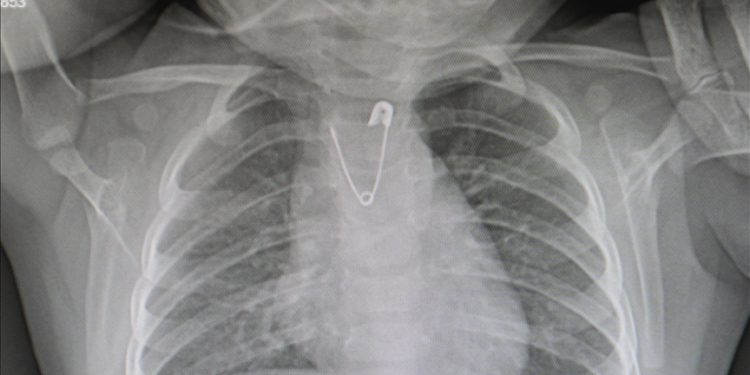

Ankara’da, yakasında bulunan çengelli iğneyi ucu açık bir şekilde yutan 10 aylık kız bebek, getirildiği Ankara Eğitim ve Araştırma Hastanesinde yapılan operasyonla kurtarıldı.